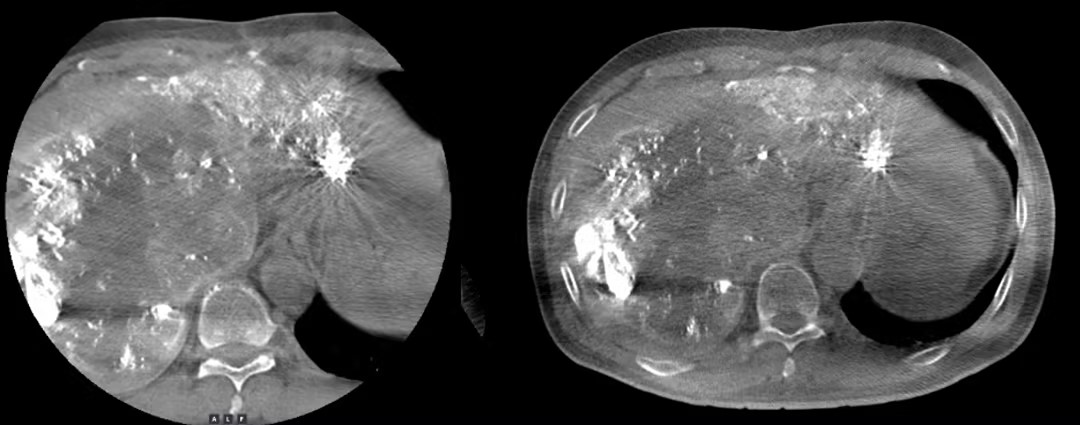

临床图像对比: 大FOV锥束CT VS 常规CBCT

过去,由于FOV(即画幅)尺寸有限,传统设备需转动好几下才能照尽肝脏,宛如“盲人摸象”一点点获取局部认知而后拼凑出全貌。“联影DSA有强大的大FOV锥束CT。在大画幅的帮助下,机器转一次就能看到整个肝脏,一次性把病灶暴露在眼前,治疗精准度和效率自然大幅提高了。”颜主任对大FOV提供的宽阔治疗视野倍感欣喜,同时指出了这一进步为患者带来的安全价值与心灵抚慰。“少检查一次、少做一次手术意味着少吃一次辐射,对患者来说肯定是更安心的。”基于“以人为本”开拓创新值域与视野,令医者和患者均能受益,才是真正从本质上诠释“医”的价值。全新视域下,技术领航的不仅仅是人体内部结构,亦是“生的方向”。与癌的对抗是一场伴随全人类生命周期的未竟之战,肉眼可见的,这场战役还在不断升级。面对强敌,以更精深、更尖端的医疗科技提气自振,是致胜的秘密武器。